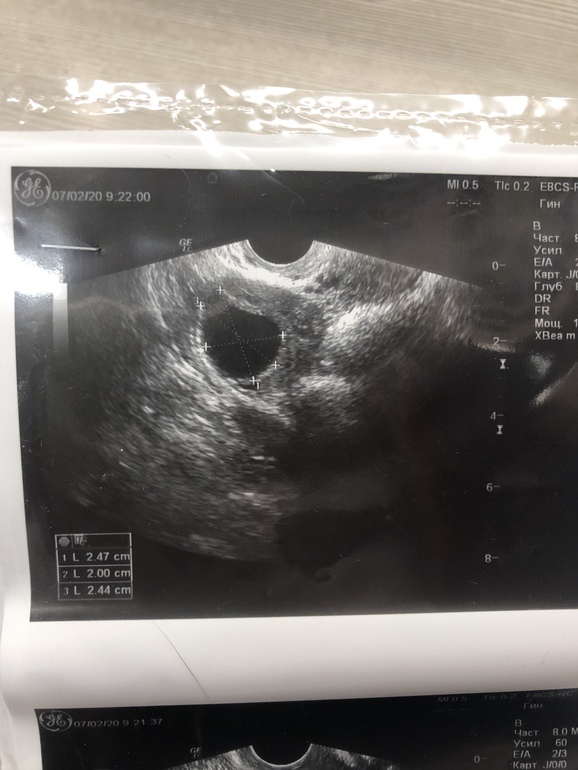

ДФ или киста фолликулярная?